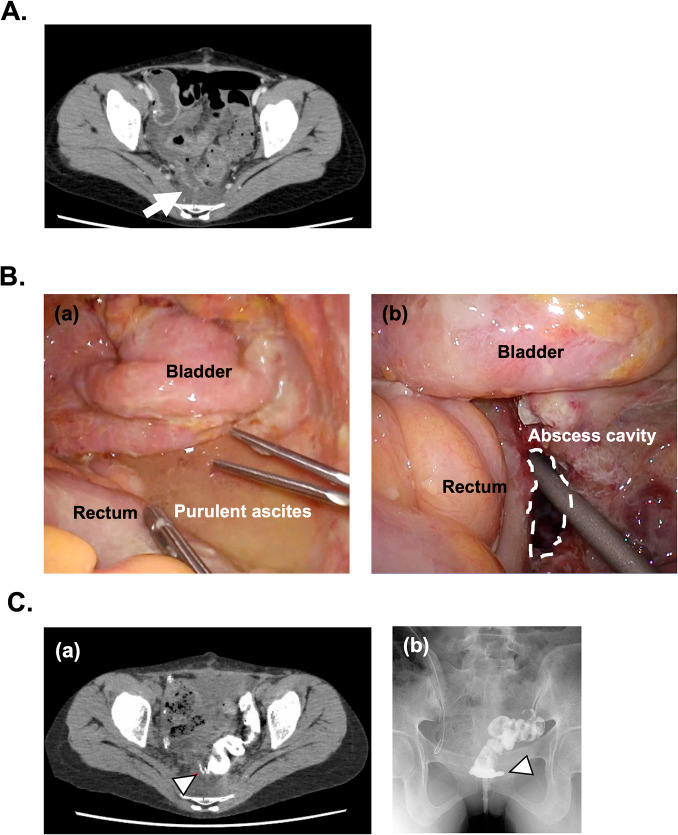

The combination therapy of lenvatinib plus pembrolizumab (LP) is increasingly recognized as an important second-line regimen for advanced or recurrent endometrial cancer (EC). However, the safety and efficacy of conversion surgery with low anterior rectal resection for unresectable EC following LP therapy is unknown. A 37-year-old woman was referred with unresectable EC with pleural fluid, peritoneal dissemination, and ascites. After the failure of first-line platinum-based chemotherapy, she was administered LP as second-line treatment. After 10 treatment cycles, uterine and peritoneal tumors significantly reduced in size, except the left ovarian metastatic tumor which became slightly larger. Cytoreductive surgery, including low anterior resection of the rectum and colorectal anastomosis, achieved complete resection. However, on postoperative day 11, the patient experienced an anastomotic leakage around the colorectal anastomosis site, necessitating a double-barreled colostomy and percutaneous drainage. She was discharged 15 days after the second surgery and resumed LP therapy after 44 days following the second surgery. We report a case in which conversion surgery after LP therapy was conducted for unresectable advanced endometrial cancer. Our findings indicate that if bowel resection is required, a longer preoperative withdrawal period may be necessary to prevent postoperative anastomotic leakage.